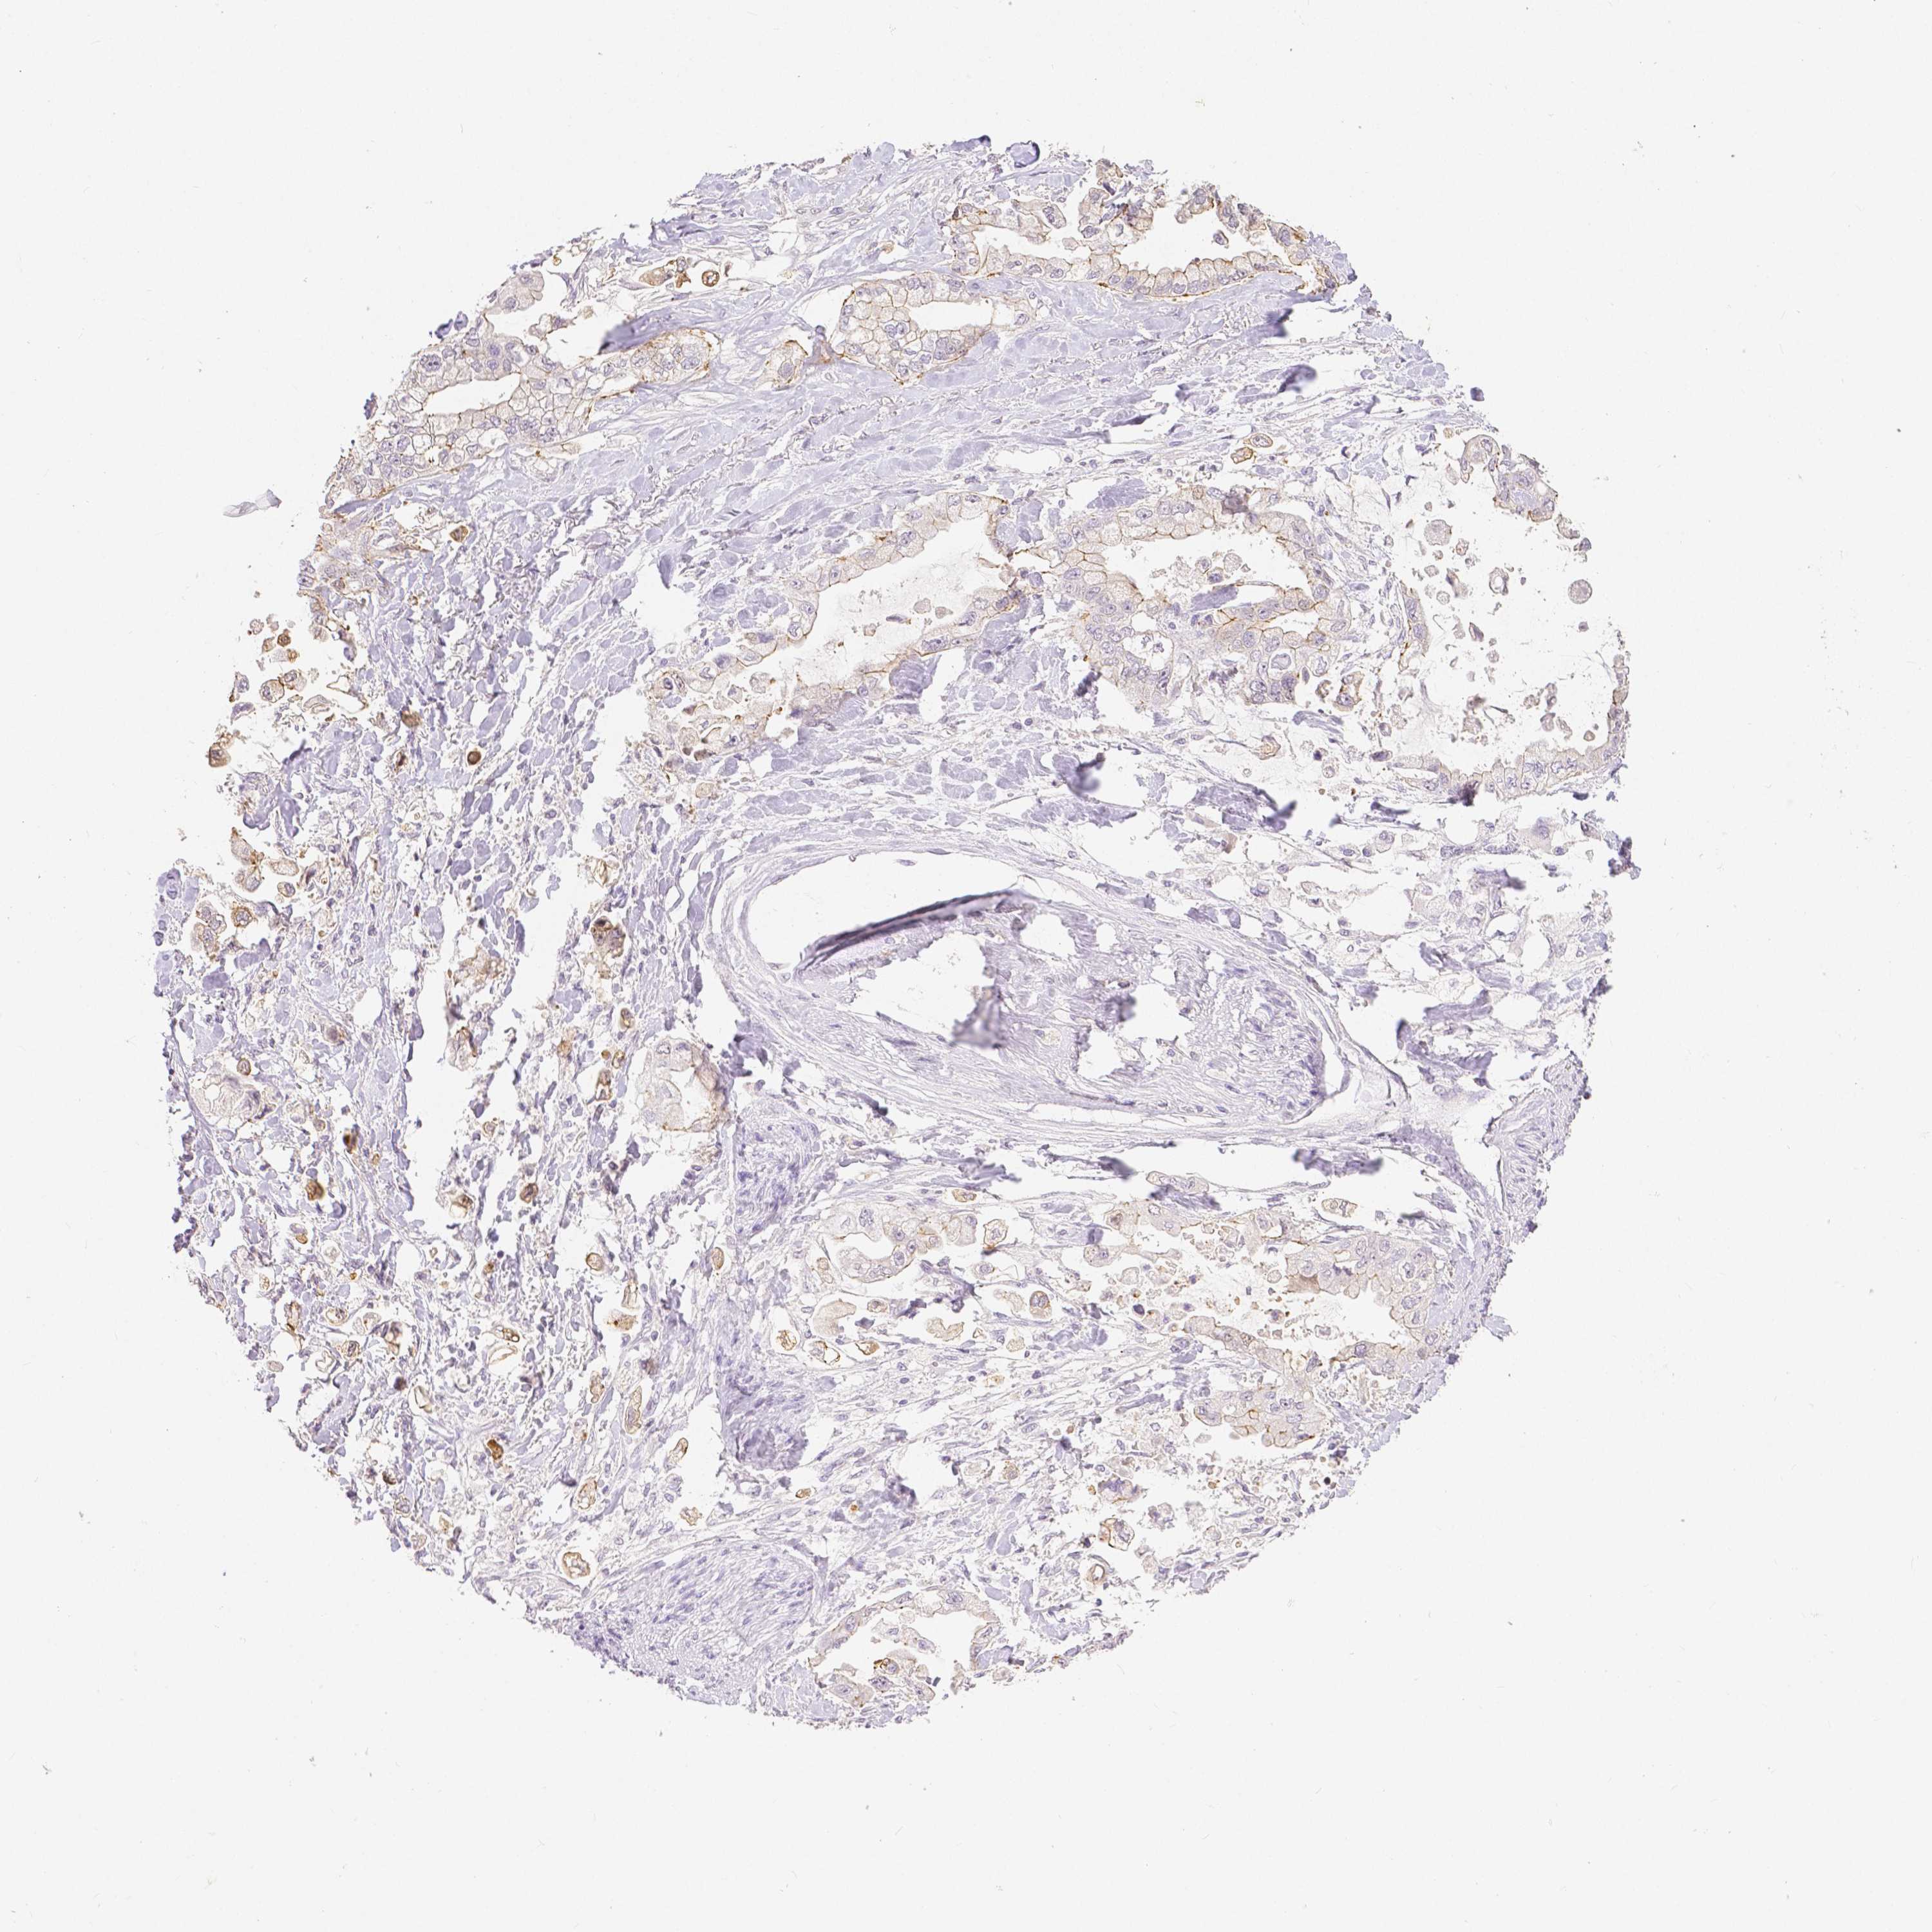

STOMACH CANCER - Protein expressioni

A mouse-over function shows sample information and annotation data. Click on an image to view it in a full screen mode. Samples can be filtered based on level of antibody staining by selecting one or several of the following categories: high, medium, low and not detected. The assay and annotation is described here.

Antibody stainingi

Antibody staining in the annotated cell types in the current human tissue is reported as not detected, low, medium, or high, based on conventional immunohistochemistry profiling in selected tissues. This score is based on the combination of the staining intensity and fraction of stained cells.

Each image is clickable and will lead to virtual microscopy that enables deeper exploration of all samples and also displays staining intensity scores, fraction scores and subcellular localization as well as patient and tissue information for each sample.

HPA005933

CAB013075

CAB068212

CAB068213

CAB068214

Staining

High

Medium

Low

Not detected

Intensity

Strong

Moderate

Weak

Negative

Quantity

>75%

75%-25%

<25%

None

Location

Nuclear

Cytoplasmic/membranous

Cytoplasmic/membranous,nuclear

Adenocarcinoma, NOS

Adenocarcinoma, High grade